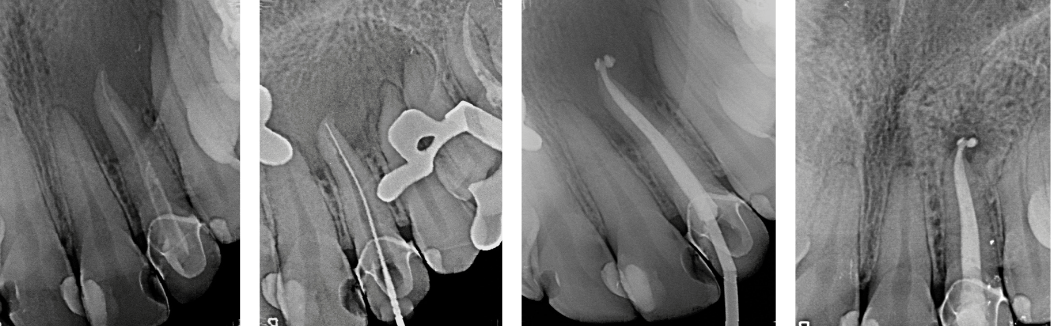

Cirugía endodóntica

¿por qué necesito una cirugía endodóntica?

En general, un tratamiento de conductos es todo lo que se necesita para salvar los dientes con pulpa lesionada de la extracción. Ocasionalmente, este procedimiento no quirúrgico no será suficiente para sanar el diente se recomendará cirugía.

La cirugía endodóntica se puede usar para localizar fracturas o canales ocultos que no aparecen en las radiografías pero que aún manifiestan dolor en el diente. Las superficies radiculares dañadas o el hueso circundante también pueden tratarse con este procedimiento.

Se hace una incisión en el tejido de las encías para exponer el hueso y el tejido inflamado circundante. El tejido dañado se elimina junto con el extremo de la punta de la raíz. Se coloca un relleno en el extremo de la raíz para evitar la reinfección de la raíz y se sutura la encía.

El hueso se cura de forma natural alrededor de la raíz durante un período de meses restaurando su función por completo.